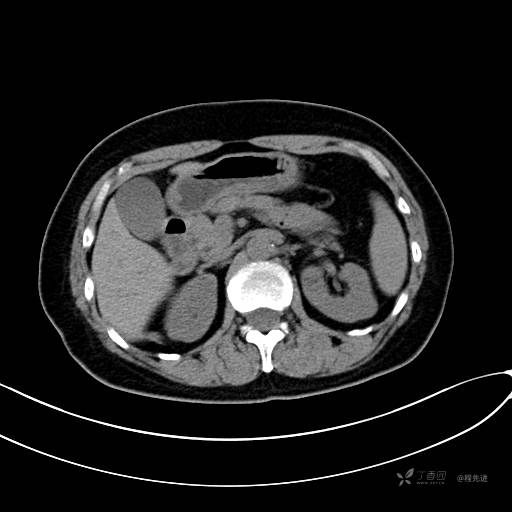

CT平扫